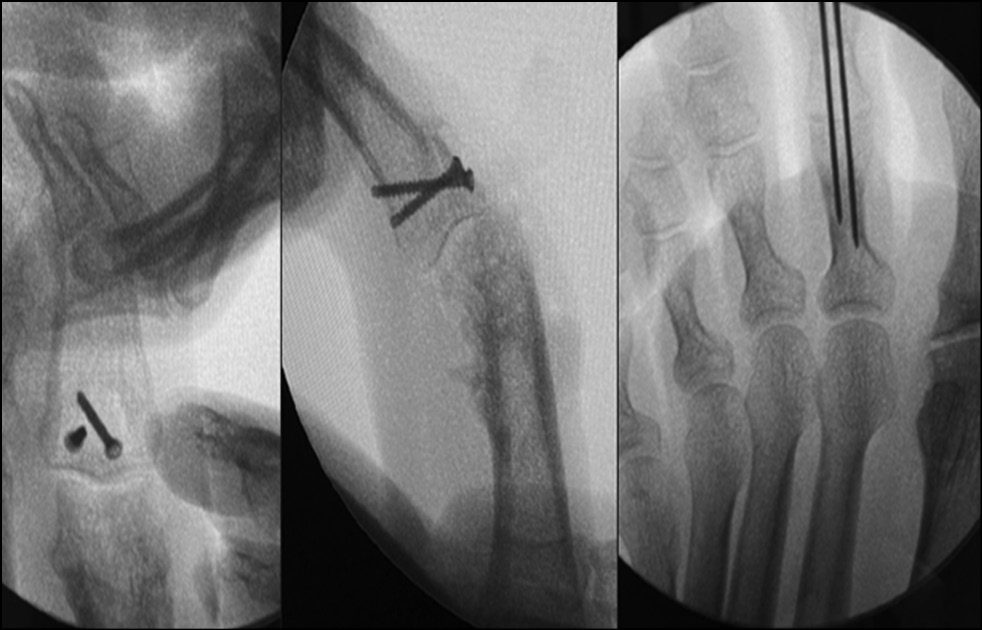

During 2021−2022, 26 patients (23 men and 3 women) with fracture dislocation of the middle phalanx base of triphalangeal fingers of hand in the acute period of trauma sought care. The average age was 31 years (16–46 years). The mechanism of injury was axial direction of force (impact) with rear deviation. All patients underwent preoperative diagnosis: radiography and clinical assessment of the amplitude of motion in the joint. Avulsive (detached) fractures of the palmar edge of the middle phalanx base with its dorsal subluxation were determined by radiologic signs. According to the Eaton classification, the patients were categorized as group IIIa. In all cases, the amplitude of movements in PIP joints was sharply limited by pain syndrome. Pain syndrome at the moment of attempted flexion in the joint was from 6 to 8 points on VAS. It was decided to treat all these patients with fixation of the injured finger in the Suzuki distraction-reposition external fixation apparatus (Figs. 24−29). This apparatus was described by Y. Suzuki in 1994 and represents t system of intraoperatively modeled three Kirschner spokes connected by rubber ties [8].

Fig. 26. X-ray control after surgery. Suzuki pins and rubber traction system.

Fig. 27. Appearance after surgery. Suzuki pins and rubber traction system.

Fig. 28. Development of active movements in Suzuki pins and rubber traction system.

Fig. 29. The results of treatment after 3 months from the date of surgery.

Intraoperatively, a 1.2 mm Kirschner spoke was inserted through the head of the proximal phalanx along the axis of rotation in the PIP joint (axial), with the ends of the spoke bent at 90°. A similar spoke is passed through the head of the middle phalanx along the axis of rotation in the distal interphalangeal joint; the ends of the spoke are also bent at 90°. Opposite bends (loops) are created at the ends of the curved shoulders of the spokes, ensuring a distance of 2.5 cm between them. Next, the third (repositioning) spoke is passed through the base of the middle phalanx as proximal as possible to the fracture zone; it is displaced to the rear relative to the phalanx axis and should pass under the shoulders of the axial spoke. Elastic rings, each 1 mm thick and cut from the rubber injection unit of an intravenous infusion system, are stretched over the bends of the first two predissected spokes. The degree of tension (distraction) of the spoke system (indicated by the number of elastic rings) is determined intraoperatively radiologically, based on size of the interarticular gap. Repositioning component of the system is accomplished by passing the middle phalanx base spoke displaced to the rear under the axial spoke. The last guided spoke is bent around the axial spoke to prevent displacement from under it but not to limit sliding between them.

Fixation in this system was carried out for 4 weeks. On day 1, the patient is trained to develop movements in the PIP joint passively. On day 2, the patient begins to perform active movements in the joint, and a radiologic control study is conducted to determine the degree of distraction and the need for its correction. It is acceptable to increase the joint gap to 4−5 mm, but the most desirable is 2−3 mm. During the outpatient phase of treatment, the patient is recommended to develop passive/active movements three to five times a day.